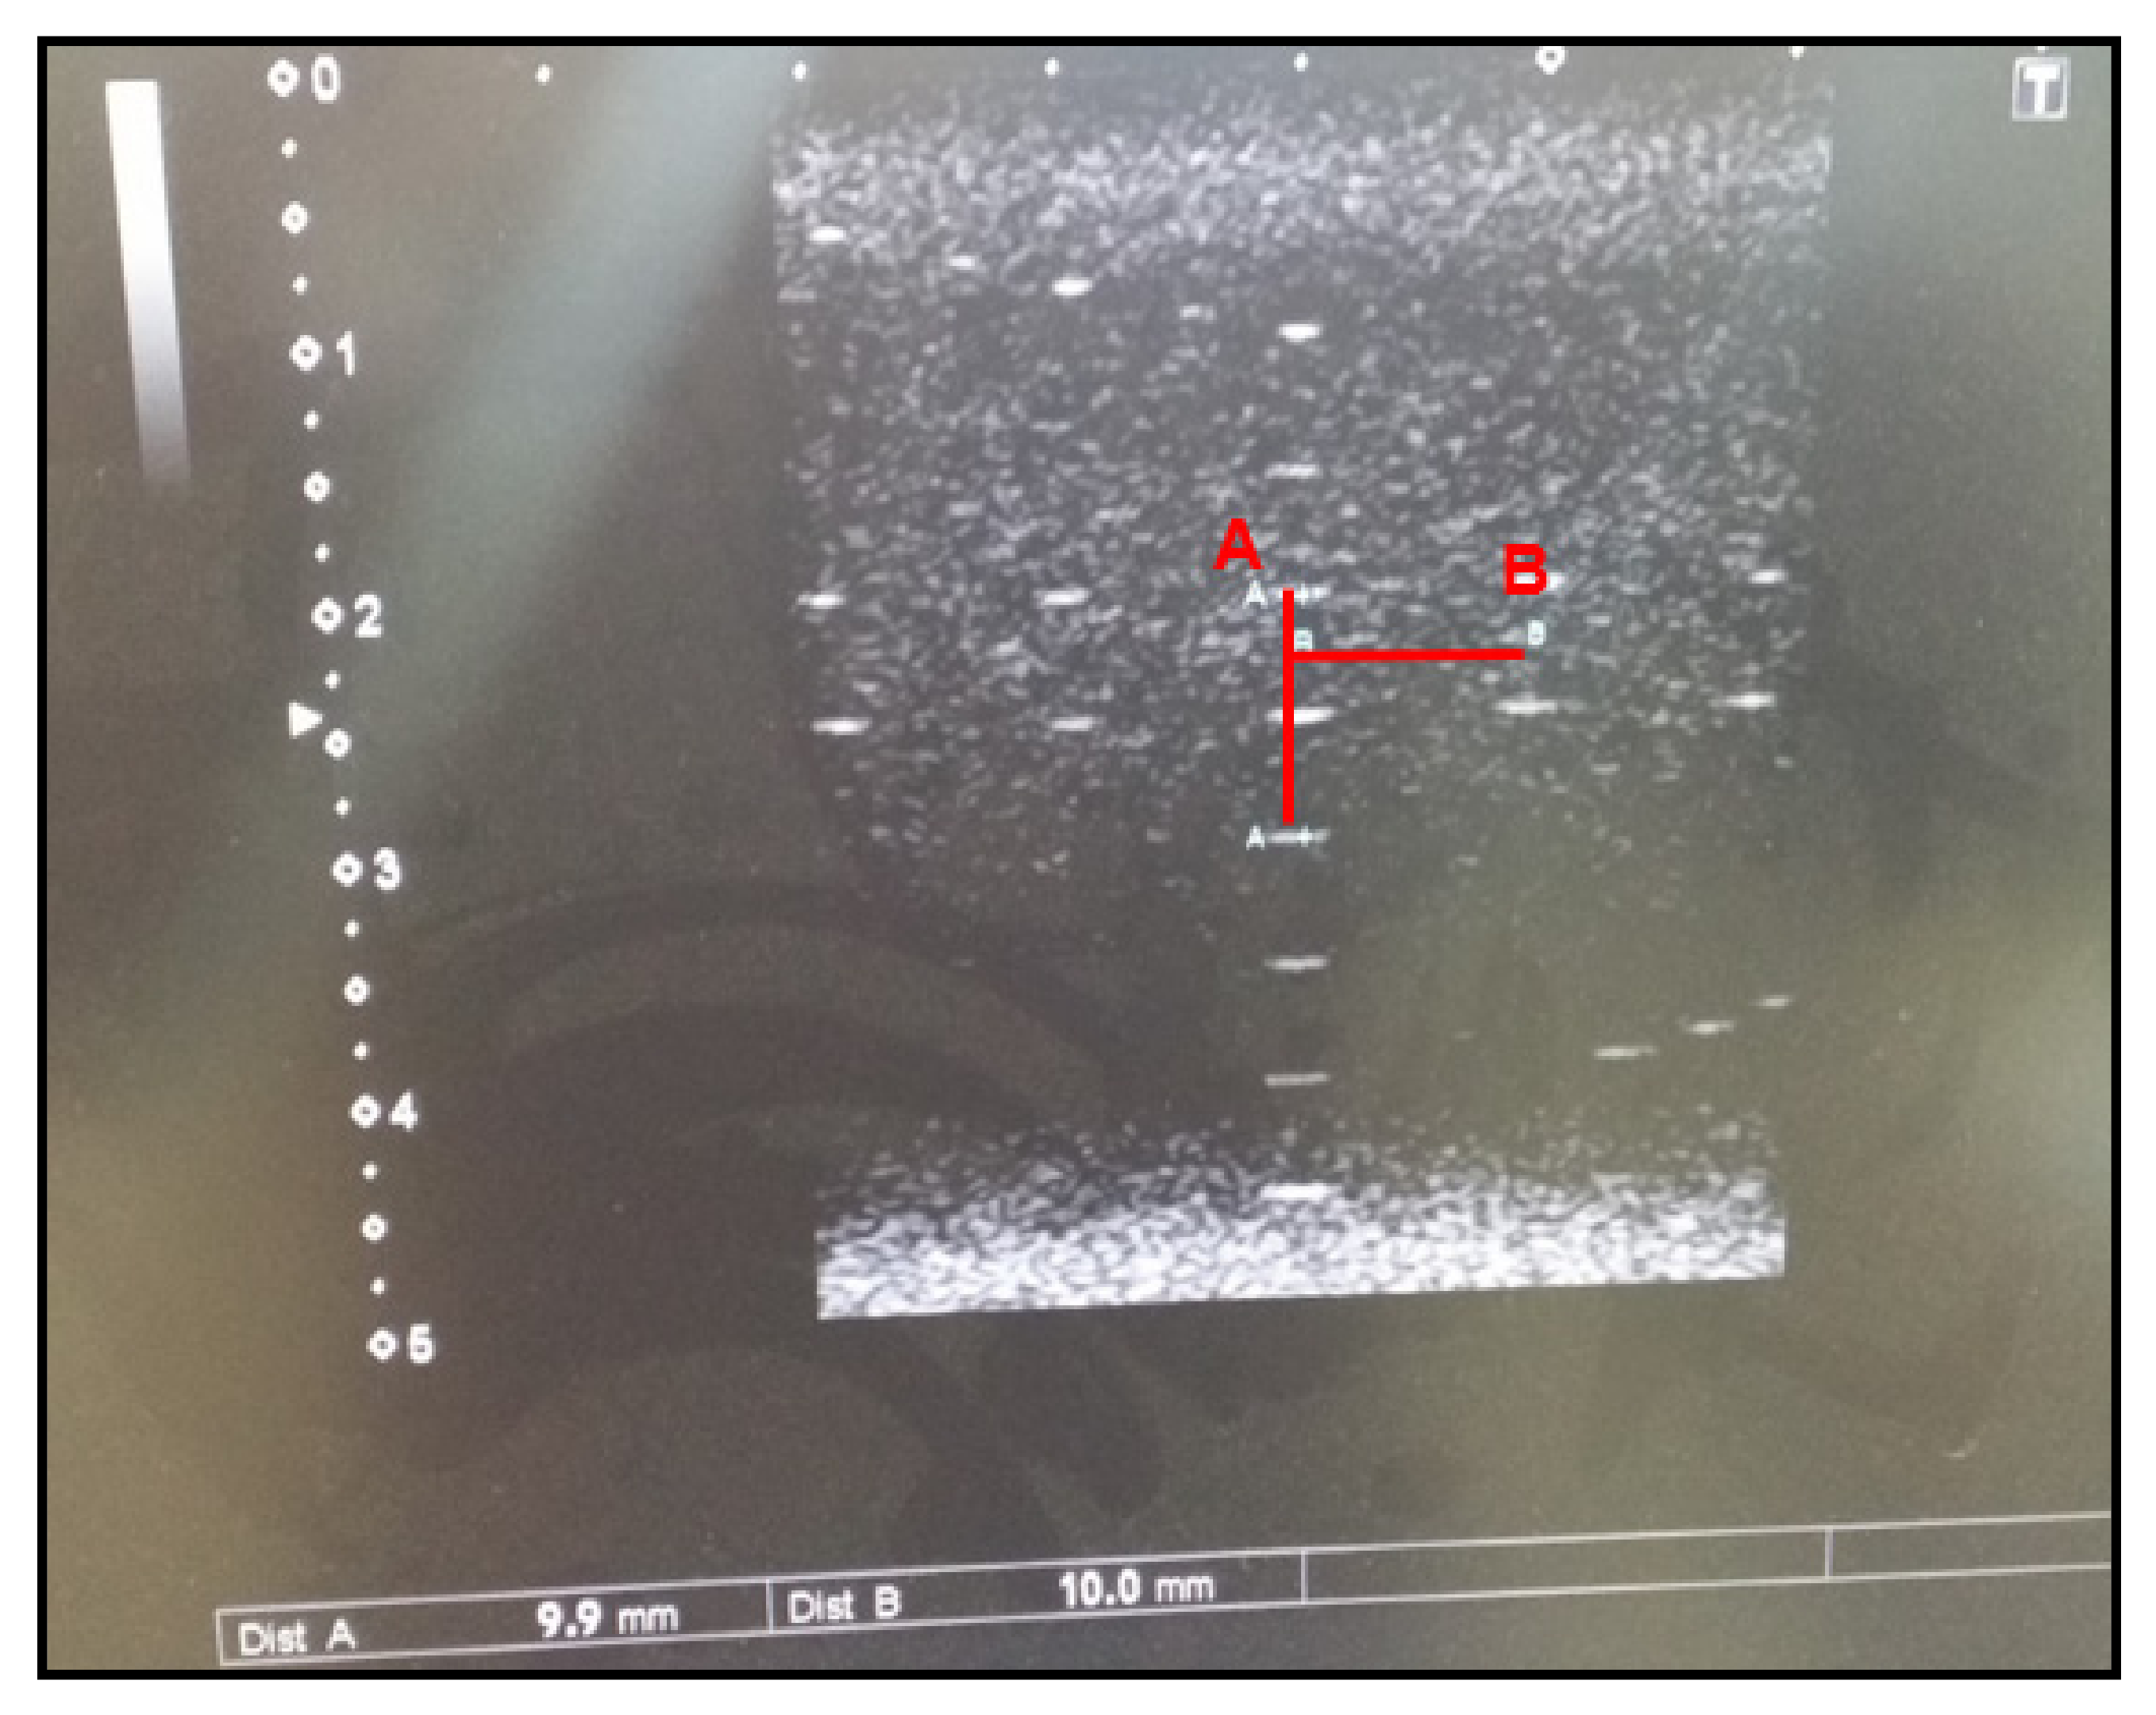

3.1.3. Resolution Test

The resolution test examines the spatial resolution of the ultrasound transducer by checking whether two distinct reflectors laying in the direction of ultrasound can be distinguished by the naked eye. Vertical resolution refers to the ability to distinguish between two reflectors that lay in front of and behind each other in the direction of ultrasound propagation, whereas horizontal resolution refers to the ability to distinguish between two reflectors that lay next to each other. A group of nine reflectors are placed in pairs 5, 4, 3, 2, and 1 mm apart, where those close to the transducer have a wider separation (Figure 3). All reflectors must be clearly distinguished. The vertical and horizontal resolution should be less than or equal to 2 mm or 3 mm, respectively, or satisfy the values suggested by the manufacturer. Our results show that both the vertical and horizontal resolutions were approximately 1 mm, which satisfied the range of the reference values.

Figure 3. (a) Ultrasound resolution, (b) Resolution distance value.